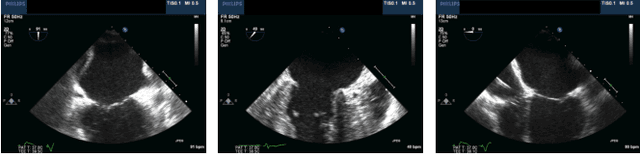

Abstract:Mitral Transcatheter Edge-to-Edge Repair (mTEER) is a medical procedure utilized for the treatment of mitral valve disorders. However, predicting the outcome of the procedure poses a significant challenge. This paper makes the first attempt to harness classical machine learning (ML) and deep learning (DL) techniques for predicting mitral valve mTEER surgery outcomes. To achieve this, we compiled a dataset from 467 patients, encompassing labeled echocardiogram videos and patient reports containing Transesophageal Echocardiography (TEE) measurements detailing Mitral Valve Repair (MVR) treatment outcomes. Leveraging this dataset, we conducted a benchmark evaluation of six ML algorithms and two DL models. The results underscore the potential of ML and DL in predicting mTEER surgery outcomes, providing insight for future investigation and advancements in this domain.